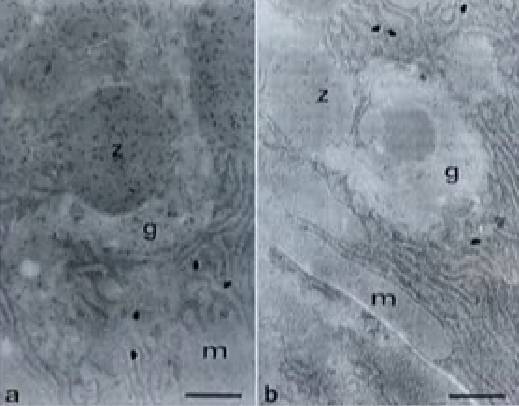

Cellules pancréatiques de rats de laboratoire vues au microscope. A gauche, alimentées au maïs non OGM. A droite, alimentées au maïs MON 863. Cette dernière coupe révèle une raréfaction d’enzymes digestives (points noirs).

Crédits : Criigen